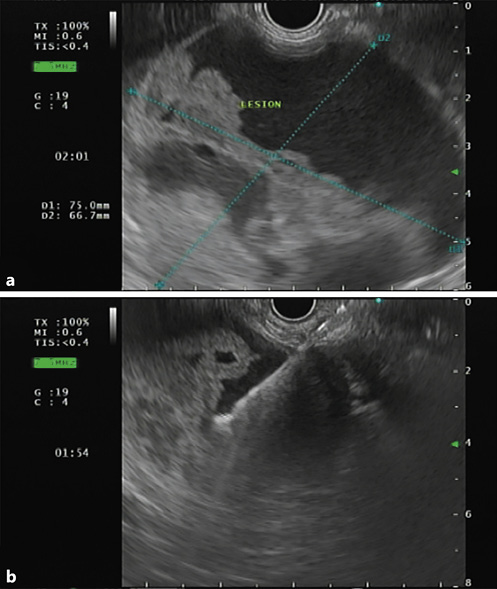

It has been discussed whether contrast-enhanced endoscopic ultrasonography (CEUS) can offer similar precision in diagnosing SPNs, compared to CECT, since it has several advantages, such as: (1) it provides real-time and dynamic imaging; (2) it does not use radiation; and (3) it can be employed in patients who are allergic to iodinated contrast media or have renal insufficiency [28]. It is becoming consensual that CEUS can, indeed, be a good alternative, as it can also show, a suggestive pattern of SPNs: (1) baseline endoscopic ultrasonography (EUS) reveals a spherical and well-demarcated lesion, with mix echogenicity (shown in Fig. 2), lacking significant blood supply; (2) CEUS shows isoenhancement during the early phase and hypoenhancement during the late phase plus lesion membrane, intralesional vessel, and intralesional compartmentalization enhancements during the arterial phase [26, 28, 29]. Nonetheless, CECT is superior to CEUS in identifying the capsule as well as intramural hemorrhage, which are the most important features for diagnosing SPN [26].

Fig. 2 a Endoscopic ultrasonography showing a large and well-demarcated lesion, located on the body and tail of the pancreas, with mixed echogenicity revealing solid and cystic components. b Fine-needle aspiration with a 19-gauge needle was performed for cytology and biochemical analysis.